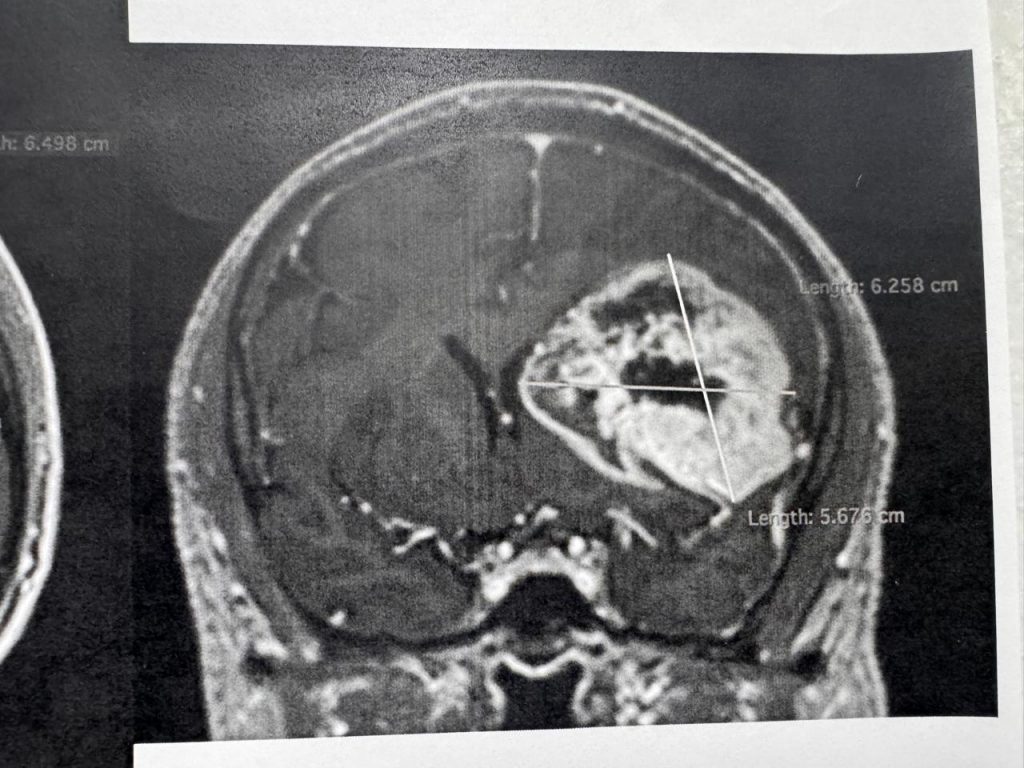

● Gracias al profesionalismo del equipo del servicio de neurocirugía del ISSSTE, un derechohabiente de 54 años recuperó habilidades de lenguaje y motricidad que perdió en dos meses debido a un tumor cerebral.

Una semana después del procedimiento de alta complejidad, el derechohabiente fue dado de alta para completar su recuperación en casa luego de que especialistas en neurología y de diversas áreas retiraron exitosamente un tumor cerebral a un derechohabiente de 54 años, quien permaneció despierto durante el procedimiento que duró siete horas en el Centro Médico (CMN) “20 de Noviembre”, perteneciente al Instituto de Seguridad y Servicios Sociales de los Trabajadores del Estado (ISSSTE).

El neurocirujano a cargo de la operación, Cuauhtémoc Gil Ortiz Mejía, informó que, en coordinación con la especialista en Neuropsicología, se decidió practicarle al derechohabiente un procedimiento llamado craneotomía con paciente despierto, a fin de regresarle las habilidades de lenguaje y motricidad que perdió paulatinamente en un lapso de dos meses por la presencia del tumor.

“El procedimiento realizado en agosto fue de alta complejidad, tuvo una duración de siete horas y se utilizó tecnología de vanguardia, como un neuronavegador cerebral,un microscopio quirúrgico, aspirador ultrasónico, craneotomo eléctrico, neuroestimulador eléctrico de la corteza cerebral, neuromonitoreo transoperatorio y equipo médico de neuroanestesia”, detalló.

Para determinar la realización de este procedimiento y conocer el orígen de los síntomas, explicó, el equipo médico del Instituto le realizó al derechohabiente estudios de tomografía y resonancia magnética.

“Se realizó tomografía de cráneo y, ante los hallazgos, se le practicó una resonancia magnética; posteriormente, se le detectó un tumor de características malignas en la región frontal premotora izquierda”, detalló.

El neurocirujano y miembro del Comité de Cirugía de Epilepsia y de Neurooncología, informó que el paciente recuperó inmediatamente sus funciones luego de la cirugía, por lo que fue dado de alta una semana después de haber sido intervenido para completar su convalecencia en casa, antes de continuar con el tratamiento complementario.

Este procedimiento se suma al realizado en julio de este año, en el que la paciente Yolitzin Salgado, de 34 años, también recuperó su salud y calidad de vida, gracias al profesionalismo del personal médico del Instituto.

Durante la intervención participaron el neuroanestesiólogo, Jesús García Cuevas; la Neuro psicóloga, Erika Graciela Meza Dávalos; así como los residentes de neurocirugía Francisco Castañeda Aguayo, Carlos Alberto Razo Vite, Salvador Guillermo Cabrera Medina; el psicólogo Diego Islas Almazán; los residentes de Anestesia, Daniela Santamaría Solís, Oscar Chimal García; la enfermera instrumentista, Carolina Reyes Iturbide; y la enfermera circulante, Gabriela López Montelongo.